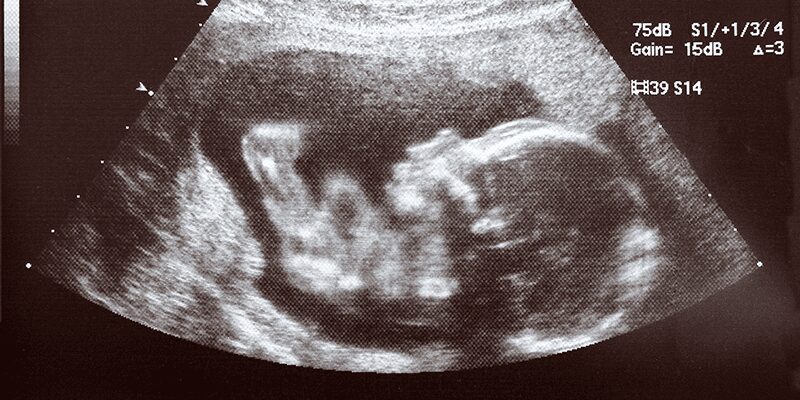

The author intended to undermine the Texas Heartbeat Act, which protects preborn babies from abortion once a child’s heartbeat is detectable. Faced with the inarguable fact that ultrasounds clearly detect cardiac activity (otherwise known as a heartbeat), the Times is forced to play word games and attempt to diminish the child’s humanity to explain why terminating the child’s life is acceptable.

The article argues that what mothers hear during an ultrasound are sounds created by the ultrasound machine translating currents into an audible noise. Fact check: true. Attempting to belittle the humanity of the preborn, the Times actually just described how an ultrasound works.

The machine transmits sound waves into the body and records the waves that echo back. The fact that technology is used to hear the heartbeat does not lessen the reality of the child’s existence. What the Times fails to explain is any true difference between what they describe as a “pulse” and a beating heart.

Commonly used ultrasound technology easily detects the existence of a child’s heartbeat as early as 6 weeks. No matter how much the New York Times or anti-Lifers try to explain this reality away with semantic games, the fact remains; a preborn child is a human child, and the Texas Heartbeat Act is saving thousands of beating hearts.